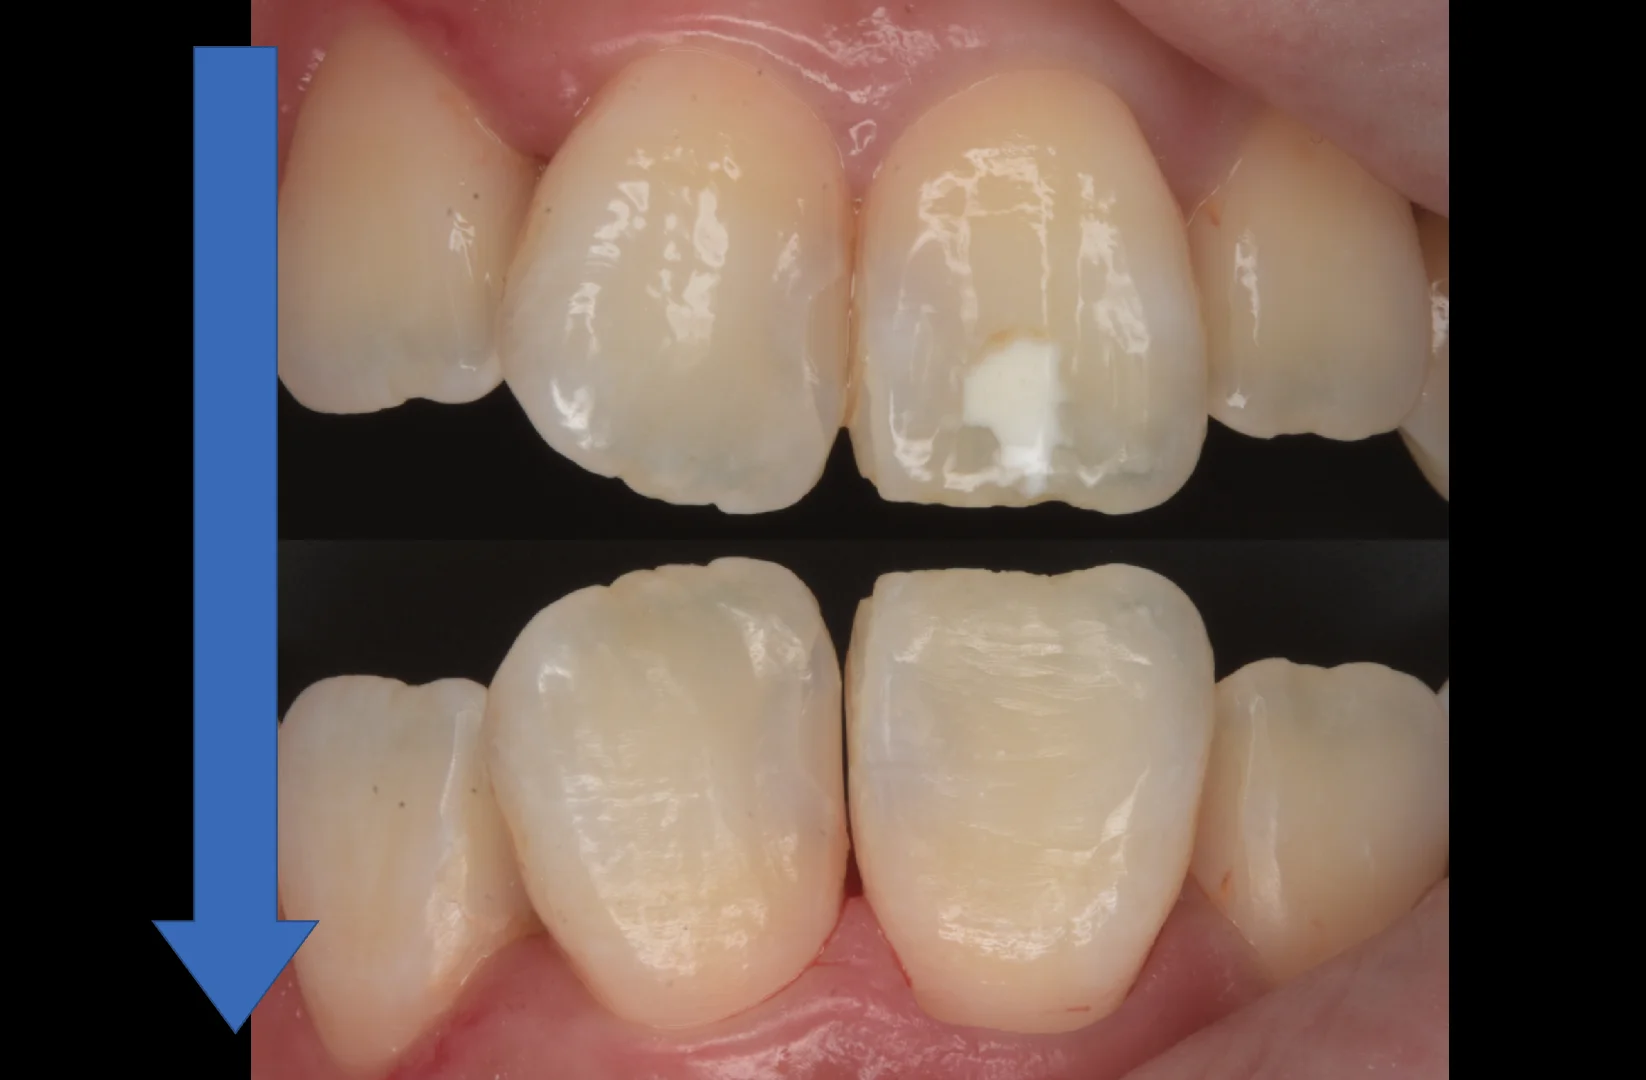

ICON治療の際に使用する強い薬剤から歯肉を守るためにつけていたゴムのマスクを外して術前術後で反転して見やすくしたのがこちらになります。

随分と目立たなく、違和感がなくなったのが分かるかと思います。

患者さん本人は長年気になっていたホワイトスポットが消えて非常に喜んでいただけました。

是非そのまま他の部分も含めて健康な状態を維持できると良いですね!

最近のレジン材料は歯ブラシを行うことで研磨をずっと行えるためツヤをしっかりと維持することができます。